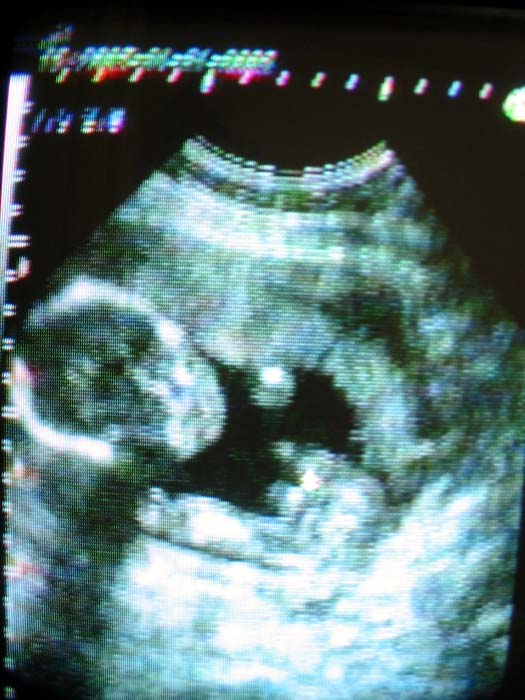

H15.4.1 産院にて

この映像はビデオ撮影をしていただいたものを

デジカメで撮影したので、画面が少し不鮮明ですが

赤ちゃんのお顔さんと手、足が写っています♪

でも、性別は・・・いつも見せてくれないので・・・(汗)

未だ、小さな小さな体を一生懸命に動かす姿は

本当に感動と感謝の気持ちでいっぱいです